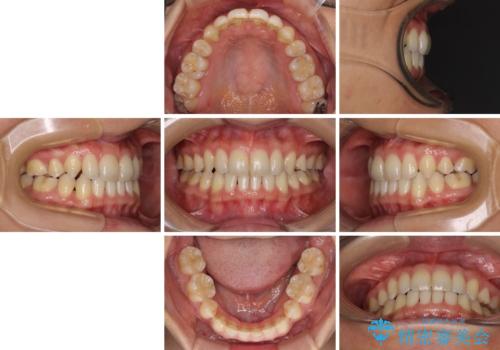

- 以前の矯正治療の後戻りにより、上の前歯にスペースができたことを気にして来院された患者様です。

インビザラインを用いて前歯のスペースを閉じつつ、上下の咬み合わせを構築していくこととしました。

隙間の空いてしまった前歯は、矯正治療で治療を行っても後戻りが起こりやすい傾向にあります。

マウスピースの保定装置をしっかりと装着しても空いてしまうため、細いワイヤーによる保定を併用することで後戻りを防止しています。